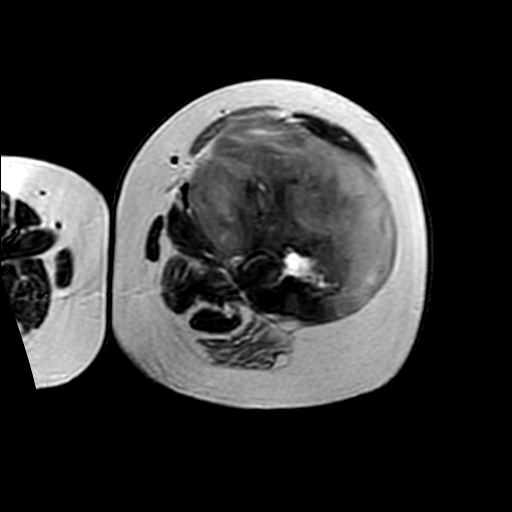

左侧大腿外伤10余年,当时情况不清,发现左侧大腿肿胀7年余,而后又有多次外伤史,近1年来出现疼痛,减重半年。查体:左侧大腿肿胀明显,皮温、肤色正常。

增强

软组织肿块,股骨破坏,增强不均匀强化-----支持恶性肿瘤